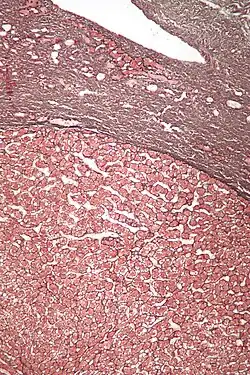

Micrograph of a hepatic adenoma (bottom of image). H&E stain

Hepatic adenomas are, typically, well-circumscribed nodules that consist of sheets of hepatocytes with a bubbly vacuolated cytoplasm. The hepatocytes are on a regular reticulin scaffold and less or equal to three cell thick.

Cells resemble normal hepatocytes and are traversed by blood vessels but lack portal tracts or central veins.